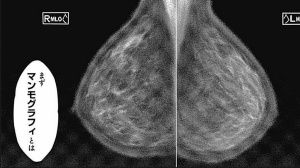

また、医療技術的な面ですが初っ端の話がMRIで、

その次がマンモグラフィーというのがマニアックですね。

最近は乳がんが巷間で話題になっている気がしますし、

そういった意味でもマンモグラフィーという題材は有りだと思います。

おっぱいを守るためにおっぱいに120Nも圧力を掛けないといけないとか、

見てるだけで痛いですがこれも必要なことなんだよなぁ…

技術的な意味での補足ですが、マンモグラフィーの被曝量が少ない理由ですが、

最近のマンモグラフィーの受像機はフィルムじゃなくてセンサーだからですね。

原理的な意味ではデジカメのCMOSセンサーと似たようなものなんですが、

X線はレンズじゃ曲がらないため撮影したい面積と同等のセンサーが必要になり、

シリコン基盤だと高価になりすぎるため液晶ディスプレイの工場で作ってたりします。